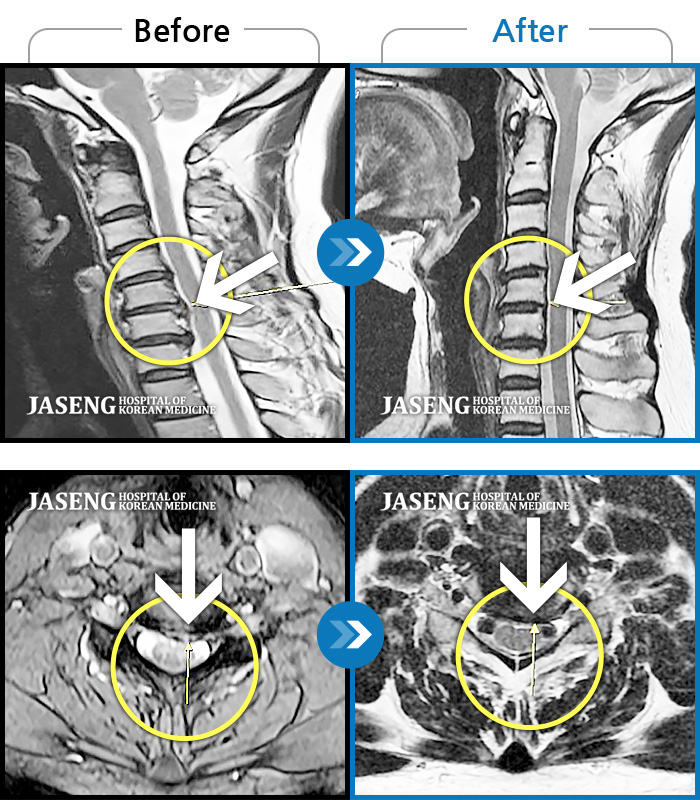

목디스크

울산 · 정운석 원장

좌측 상완 외측, 하완 외측, 수부 전체 통증 및 저림

촬영시기

2021.06.07 ~ 2021.05.25

2021.06.04